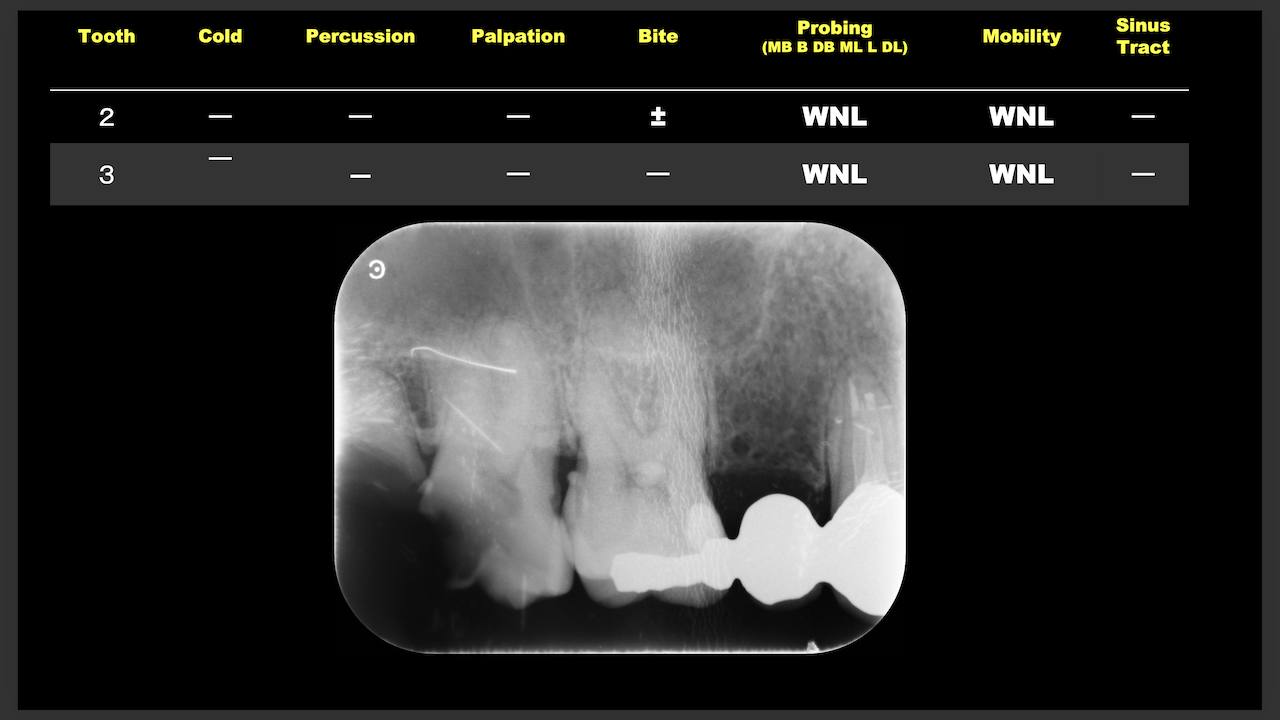

Sinus tractがある歯牙の再根管治療だ。

DB根はすでに切断されている。

が、逆根充がなされていない。

DBは根切済みだ。

Pにも病変がある。

ということは、再根管治療だろう。

ただ、予後はGuardedだ。

なぜか?根切がうまく行っていないからだ。

臨床的にDB

この後、

Sinus tractは消失した。

3ヶ月経過した。

DBの病変が小さくなっている。

Pは病変が大きくなっていうように見えるがまだわからない。

ということで、切ることだけが全てでないということを証明してくれた。